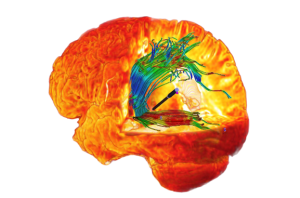

Software para Tractografia

O Software Eximius permite o mapeamento dos tractos por meio de sementes que determinam a área de interesse do cirurgião. Informações Valiosas sobre o trajeto e direção das fibras auxiliam a abordagem cirúrgica.

Associando recursos de computação avançada com imagens médicas de qualidade, as ferramentas disponíveis no Software Eximius Med permitem as seguintes funções:

- Análise das imagens de ressonância magnética por tensor de difusão (DTI);

- Importação de múltiplas séries com posicionamento automático;

- Edição de tractos com renderização em tempo real;

- Seleção dos tractos de interesse através do posicionamento de múltiplas sementes;

- Fusão dos tractos com as imagens de base da tomografia ou ressonância magnética;